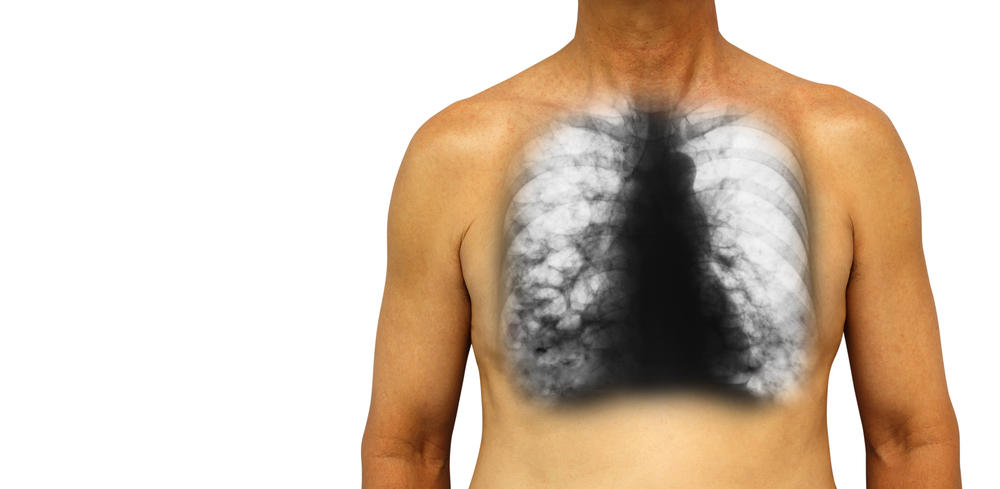

ब्रोन्किइक्टेसिस (Bronchiectasis) एक ऐसी स्थिति है, जिसमें हमारे फेफड़ों की (bronchial tubes) ब्रोन्कियल ट्यूब्स स्थायी रूप से क्षतिग्रस्त, चौड़ी और मोटी हो जाती हैं। इन क्षतिग्रस्त के कारण फेफड़ों में बैक्टीरिया और बलगम का निर्माण होता है और यह इन्फेक्शन या एयरवेज में ब्लॉकेज का कारण बनते हैं। इससे हमें सांस लेने में भी परेशानी होती है। ब्रोन्किइक्टेसिस (Bronchiectasis) एक लंबे समय तक चलने वाली बीमारी है, जो समय के साथ बदतर हो सकती है। इसका कोई इलाज नहीं है, लेकिन आप कुछ सावधानियां बरत कर इसके लक्षणों को कम कर सकते हैं। ऐसे में, इस समस्या से बचाव और उपचार से पहले इसके लक्षणों के बारे में पता होना जरूरी है। जानिए इस बीमारी के बारे में विस्तार से:

चेस्ट कंप्यूटेड टोमोग्राफी स्कैन (A chest computed tomography scan), या छाती का सीटी स्कैन, ब्रोन्किइक्टेसिस (Diagnosis of Bronchiectasis) के निदान के लिए सबसे आम टेस्ट है, क्योंकि छाती का एक्स-रे (chest X-ray) पर्याप्त जानकारी प्रदान नहीं करता है। यह टेस्ट रोगी के एयरवेज और छाती में अन्य संरचनाओं की सही तस्वीरें बनाते हैं। एक चेस्ट सिटी स्कैन अच्छे से बता सकता है कि फेफड़ों को कौन सी जगह पर कितना नुकसान हुआ है।